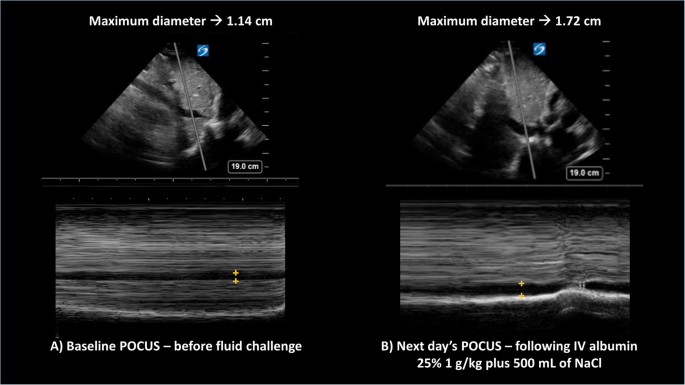

In inpatients with AKI, where intra-vascular volume status is uncertain, point-of-care-ultrasound (POCUS) plays a pivotal non-invasive role and helps formulate a sound clinical plan based on real-time physiologic evidence32. Routinely performing POCUS to evaluate the inferior vena cava (diameter/percent collapsibility) and lung edema (B-lines) can inform fluid resuscitation and prevent overt pulmonary edema in AKI (Fig. 2)33,34. Unlike outpatients where there is guidance on diuretics titration, in inpatients admitted for anasarca, it is unclear when rapid mobilization of fluid through forced diuresis can results in AKI. Here, POCUS might also become a useful tool to prevent prerenal AKI, maximize diuretic therapy, and reduce length of hospital stay. Finally, for patients with confirmed HRS, terlipressin should be started as soon as diagnosis has been made, with the understanding that there is a high risk of HRS recurrence in respondents and that the true definitive treatment is LT33. Patients with HRS-AKI should be prioritized for LT with the aim of preventing further renal disease progression in need for simultaneous liver-kidney transplant (SLKT). Undoubtfully, preventing recurrent AKI is a priority to decrease the chance of progressing to chronic kidney disease (HRS-CKD) and needing SLKT35.

For both panels, the top section shows the liver and the inferior vena cava (IVC) in B-mode ultrasound, whereas the bottom panels represent the M-mode trace for the superimposed gray line sampled from above. On the M-mode, the horizontal dark column represents the IVC maximum diameter (+orange marks). Panel A to the left corresponds to the baseline evaluation prior to starting the fluid challenge, when the maximum diabetes was 1.14 cm, whereas Panel B shows an increase in diameter to 1.72 cm following intravenous (IV) albumin and normal saline (NaCL). In both cases, the sniff test showed a calculated collapsibility ≥50%. The change from panel A to panel B suggests improved intravascular volume status.